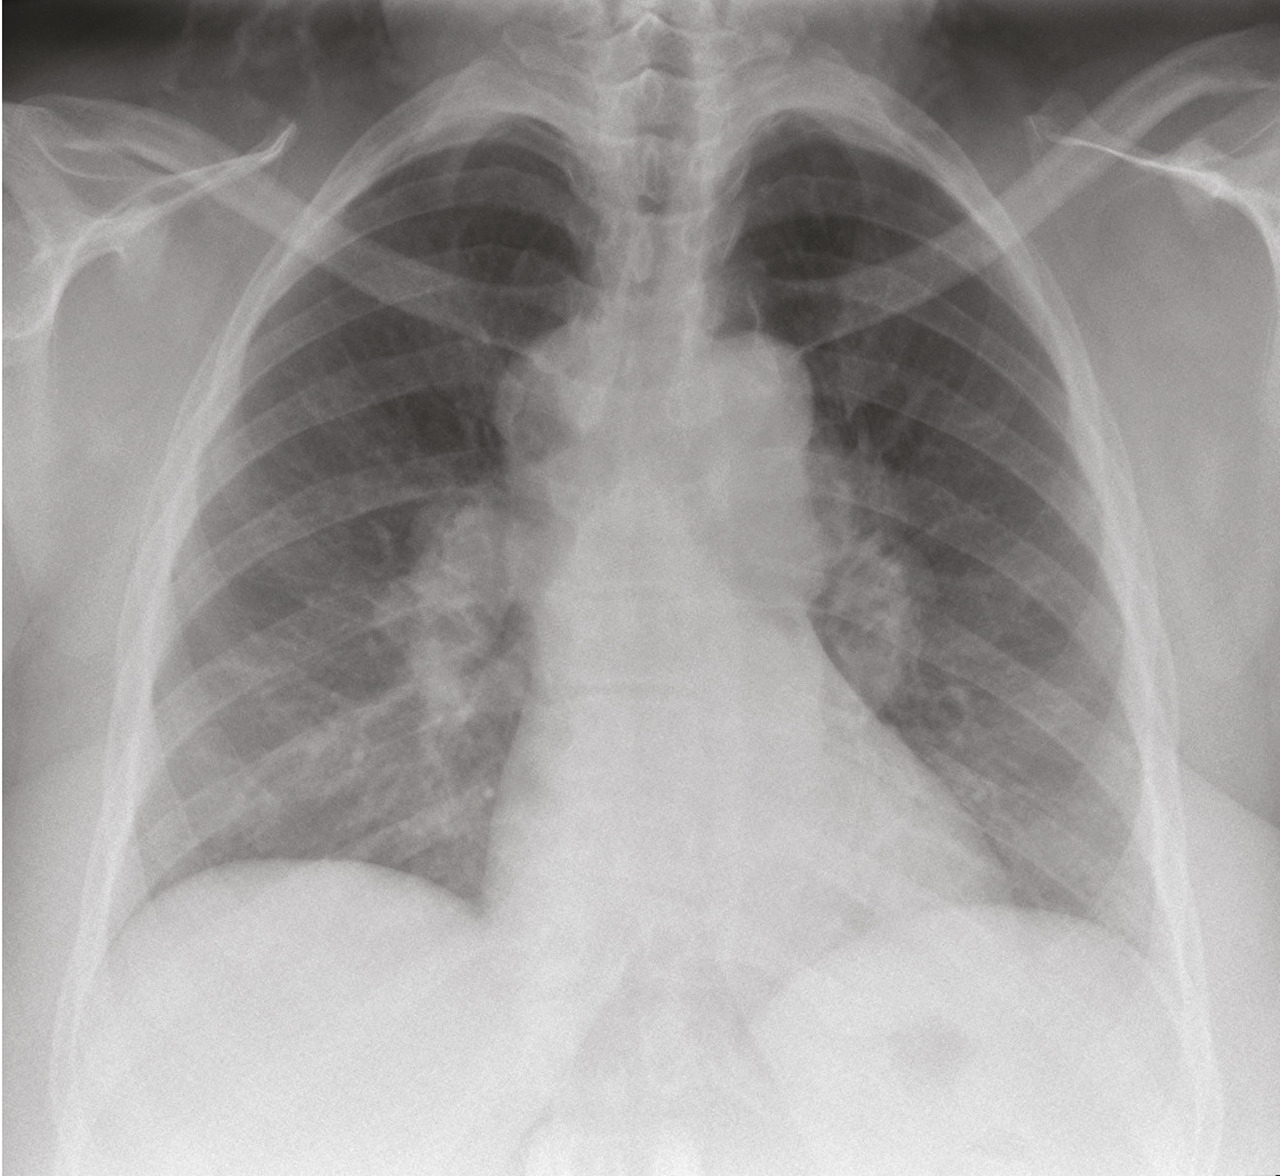

La radiographie thoracique est essentielle au diagnostic et pour le suivi de la maladie, elle est anormale dans 90 à 95 % des cas.32 Certains signes sont typiques et présents dans 50 à 80 % des cas : les adénopathies hilaires bilatérales symétriques et non compressives (fig. 1). La présence d’adénopathies médiastinales, sans atteinte hilaire ou unilatérale, est très atypique et doit faire rechercher un diagnostic différentiel (cancer, hémopathie, tuberculose). L’infiltration parenchymateuse, si elle est présente, prédomine dans les territoires supérieurs et moyens. La classification de Scadding distingue 5 stades corrélés avec la probabilité de guérison spontanée de la sarcoïdose :